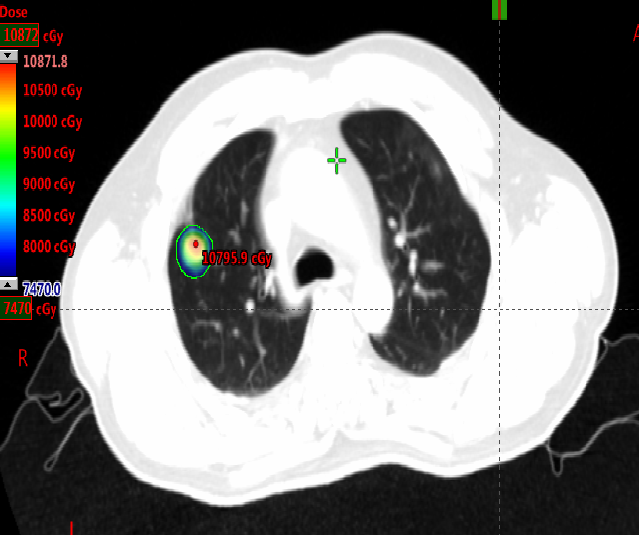

局部治疗(二):SBRT治疗

2020-11-6至2020-11-25 左肺下叶及右肺下叶转移灶放疗:95% PTV1-2 74.7Gy/4.98Gy/15F。

2020-12-31至2021-1-19右肺上叶转移灶放疗:95% PTV 74.7Gy/4.98Gy/15F。

SBRT疗效评价:部分缩小。

三线治疗

2021-1 起口服呋喹替尼3mg +曲妥珠单抗。

期间2021-3-15胸部CT:双肺转移瘤部分较前略增大,疗效SD。

三线治疗疗效评价:部分增大,PD。